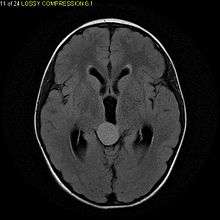

Pilocytic astrocytomas are often cystic, and, if solid, tend to be well-circumscribed. It is characteristically easily seen on CT scans and MRI.

Usually—depending on the interview of the patient and after a clinical exam which includes a neurological exam, and an ophthalmological exam—a CT scan and or MRI scan will be performed. A special dye may be injected into a vein before these scans to provide contrast and make tumors easier to identify. The neoplasm will be clearly visible.

Macroscopically, an astrocytoma is a mass that looks well-circumscribed and has a large cyst. The neoplasm may also be solid.

Under the microscope, the tumor is seen to be composed of bipolar cells with long "hairlike" GFAP-positive processes, giving the designation "pilocytic" (that is, made up of cells that look like fibers when viewed under a microscope[8]). Some pilocytic astrocytomas may be more fibrillary and dense in composition. There is often presence of Rosenthal fibers,[9] eosinophilic granular bodies and microcysts. Myxoid foci and oligodendroglioma-like cells may also be present, though non-specific. Long-standing lesions may show hemosiderin-laden macrophages and calcifications.